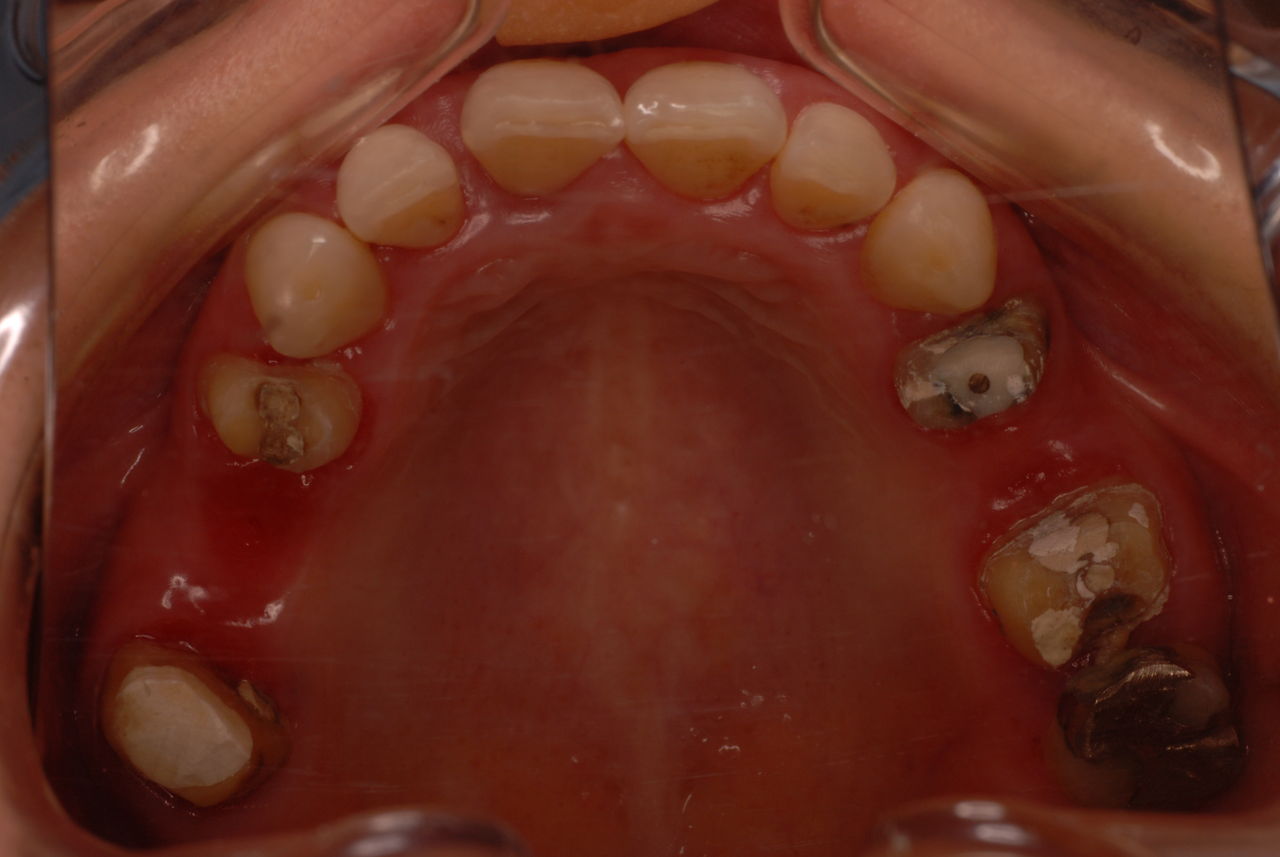

お口の中から差し歯、入れ歯、詰め物を追放しましょう!

口の中の病気を治し、病気を興さない医療を目指します。

二度とお口の中へ変なものを入れなくても済むように

予防に精進いたしましょう!安全な矯正、美容を目指しましょう!